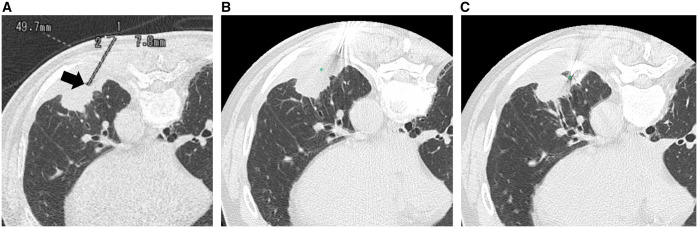

Abstract Image